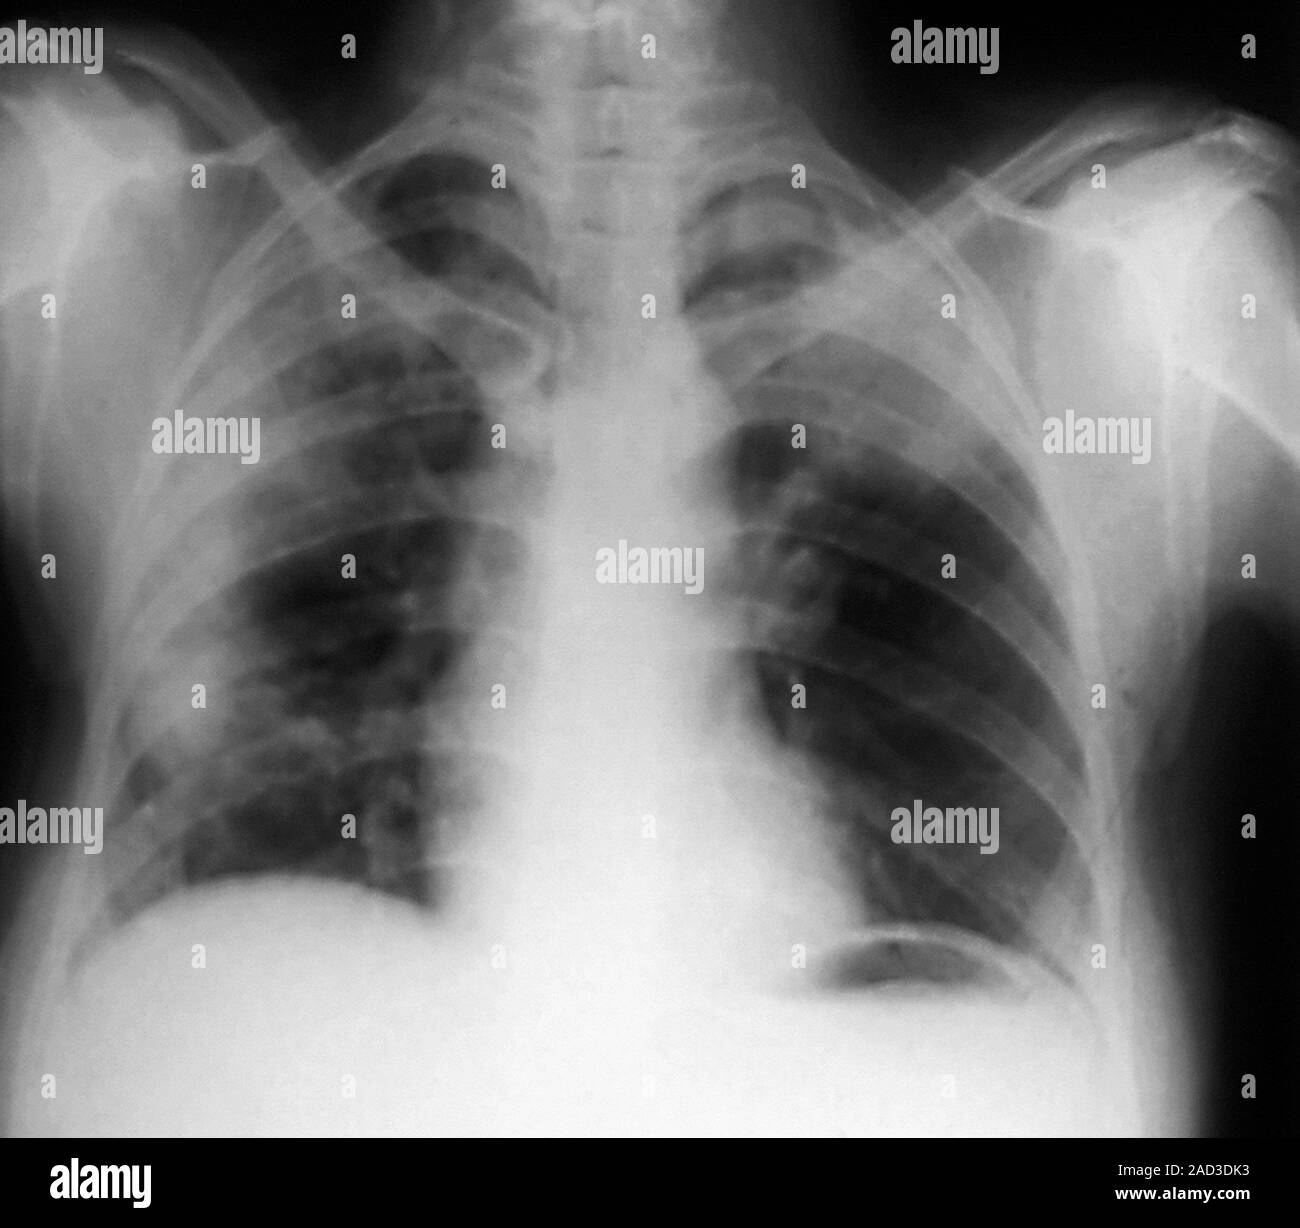

From www.alamy.com

Abdominal air pockets. Chest Xray of a 44 year old patient showing air Air Pocket Lung A pneumothorax is an accumulation of air or gas in the space between the lung and the chest wall that occurs when a hole develops in the lung that allows air to escape. Bullae, or air pockets within the lung tissue are more commonly associated with chronic disease processes such as chronic obstructive pulmonary disease (emphysema). This causes the lung. Air Pocket Lung.

Abdominal air pockets. Frontal chest Xray of a 62yearold patient Air Pocket Lung This causes the lung to partially or completely collapse, hence the condition's other name: Learn more about how doctors diagnose and treat air trapping here. Pneumomediastinum is air or gas in the space between your lungs (mediastinum). Bullae, or air pockets within the lung tissue are more commonly associated with chronic disease processes such as chronic obstructive pulmonary disease (emphysema).. Air Pocket Lung.